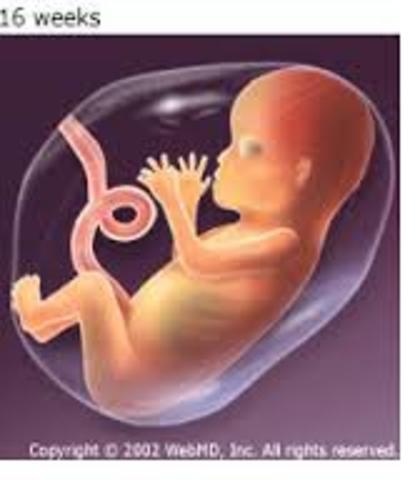

• 4th Month

4th Month

1. You can feel the baby move.

2. The baby's skin is pink.

3. The umbilical cord and placenta works.